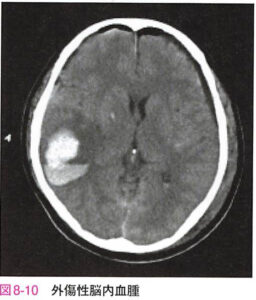

| 外傷性脳内血腫 | 脳挫傷による小出血が癒合し、脳内血腫に進展して形成されることが多い(多くは72時間以内)![]() |

|

脳挫傷・外傷性脳内血腫

| 病態 | 脳実質損傷のこと。脳挫傷による小出血が癒合し、脳内血腫に進展して形成されることが多い。 ※出血部位が前頭葉や側頭葉にあることが脳出血との鑑別点に有用 |

| 検査 | 頭部CT:時間経過とともに冠状断像でごま塩状の変化が見られることがある![]() |